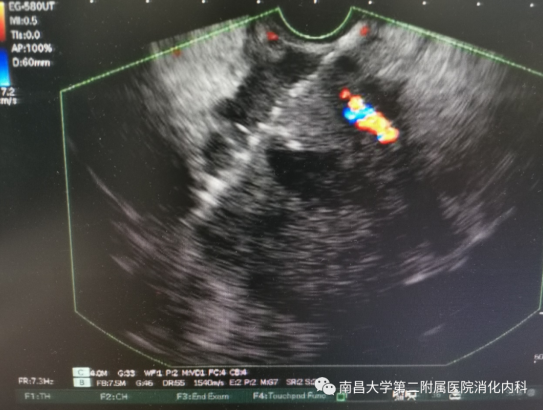

超声内镜引导下肿瘤内碘125粒子植入

一切准备就绪后,在章诺贝副教授具体实施、核医学科刘俊主治医师和消化内科刘必成护师的配合下,团队依靠超声内镜定位病灶,测量病灶大小,做好术中规划,避开重要血管,选择最佳穿刺路径,在超声内镜引导下精准植入碘-125粒子18颗,手术顺利, 操作过程患者无不适,术后安返病房,恢复良好。复查CT可见粒子分布良好,布道合理。